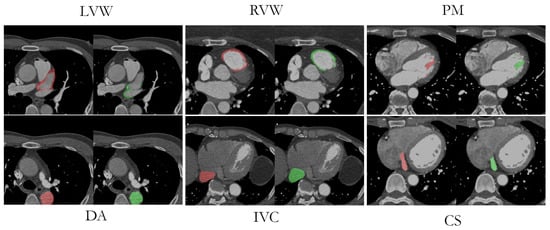

Visual comparisons between the original image, the manual labeling, and the AB-ResUNet+ model prediction are shown in Figure 8. The segmentation prediction examples and GT overlays over the original image for LVW, RVW, PM, DA, IVC, and CS more accurately illustrate the potential difficulties in segmentation due to low image quality, high and low contrast differences, and the highly anatomical complexity of the structures. The difficulty in identifying the irregularly shaped CS, especially with suboptimal contrast fluoroscopy, may account for the lower accuracy compared to the other vessels. The complex structure of LVWs and RVWs, which varies in different layers and in different patients, makes them a particular challenge for automatic segmentation methods.

Figure 8.

An example of original images from LVW, RVW, PM, DA, IVC, and CS dataset with an overlay of successful segmentation prediction (red) and corresponding GT (green).